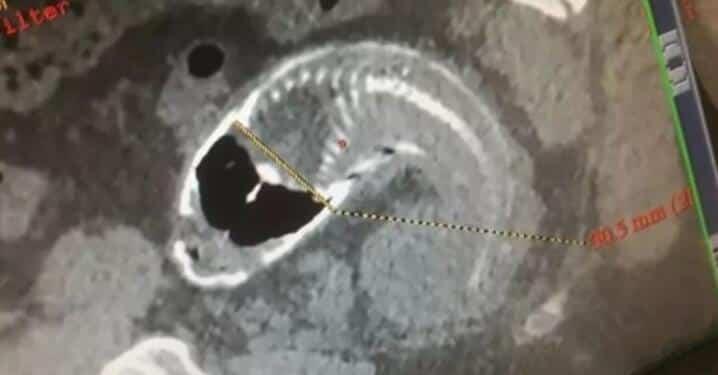

psari

Οι αξονικές τομογραφίες αποκάλυψαν ότι το ψάρι ήταν κολλημένο στο ορθό, με τον ασθενή να παραπονιέται για έντονο κοιλιακό άλγος που διήρκεσε πάνω από μία ώρα, σύμφωνα με αναφορές στις 5 Ιουνίου. Η ακτινογραφία ανατριχιάζει, όπως και αυτή ενός άλλου άνδρα που είχε επίσης πόνους στην κοιλιά.

Ο άντρας έπρεπε να κάνει ενδοσκόπηση έκτακτης ανάγκης – οι εικόνες δείχνουν τον σκελετό του ψαριού στον ορθό του. Η έκθεση ανέφερε επίσης ότι οι γιατροί προσπάθησαν επανειλημμένα να βγάλουν το ψάρι, αλλά ήταν πολύ μεγάλο.